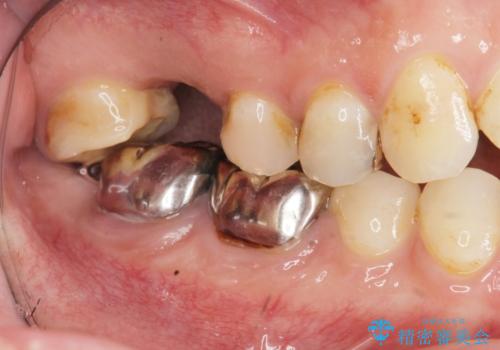

銀歯の下に大きな虫歯の再発

「 セラミック治療 」奥歯を白くしたい